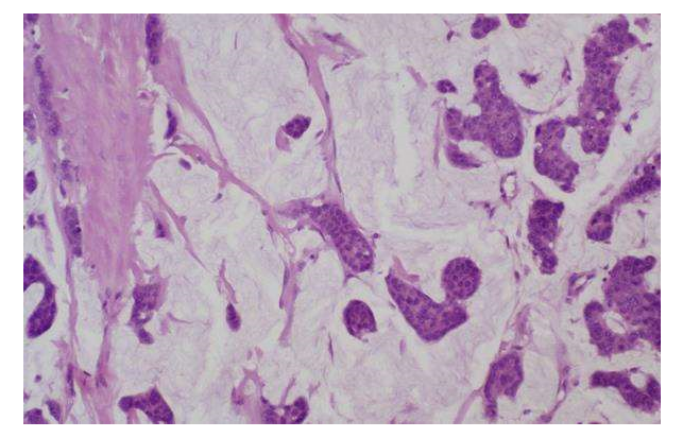

colloid mucinous carcinoma mamogram, gross, microscopy

well circumscribed and lobulated

soft, pale blue gelatinous surface

cells nested in pools of mucin